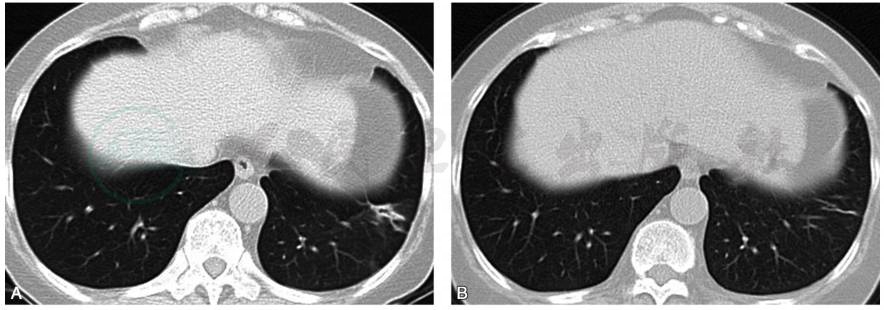

患者口服糖皮质激素30mg/d,1个月后复查胸部CT提示左下肺病灶明显吸收,残留少许条索影;激素减量口服治疗半年,2017年11月2日复查胸部CT提示左肺下叶病灶完全吸收(图3)。遂停药观察。

图3 复查胸部CT

A.口服糖皮质激素30mg/d,1个月后复查胸部CT(2017-6-23)提示左下肺病灶明显吸收,残留少许条索影;B.激素减量口服治疗半年,复查胸部CT(2017-11-2)提示左肺下叶病灶完全吸收